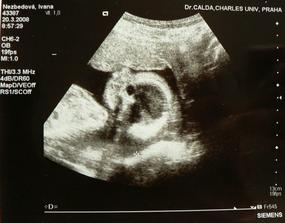

Ve 21tt jsme byli na druhy velky ultrazvuk i s tatkou, miminko je krasne a zdrave a hlavne ma vysnenyho pindika 🙂 Dokonce uz zacinam i pribirat, ve 22tt mam 4 kila nahore. Pomalu zacneme nakupovat vybavicku, nejake oblecky a pomucky (nuzky, teplomer, lahvicku, podlozku na koupani a do postylky) uz mame, vybrali jsme si i kocarek, jen s plenkama se porad nemuzu rozhodnout jestli budem pouzivat jednorazovky nebo plenkove kalhotky...